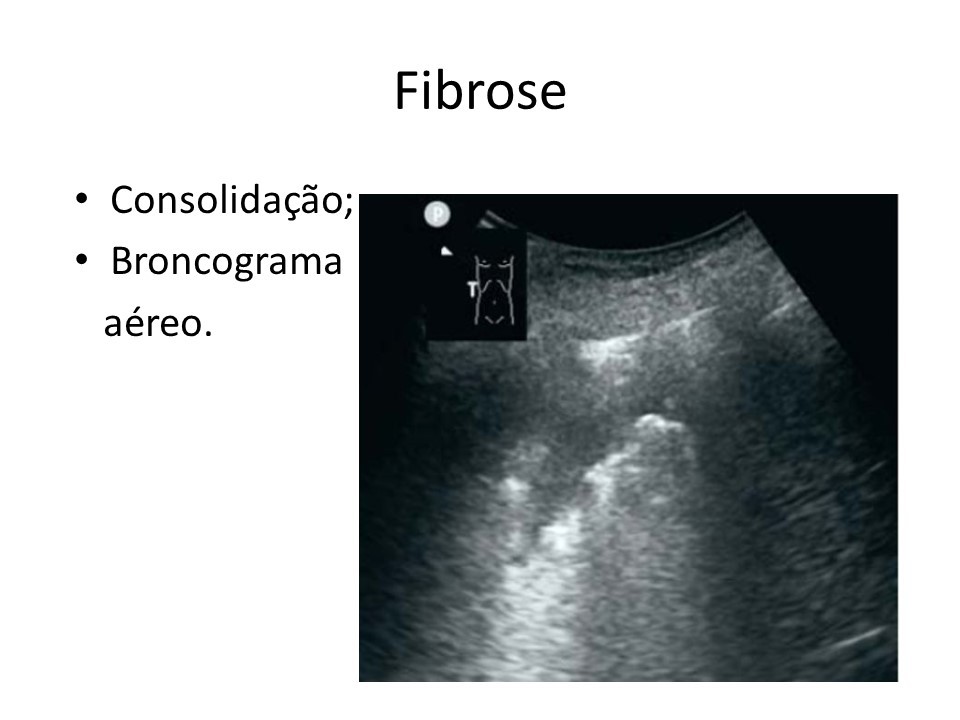

Página Inicial Imagem de ultrassom mostra marcas em pulmão com fibrose causada pelo coronavírus (Divulgação)